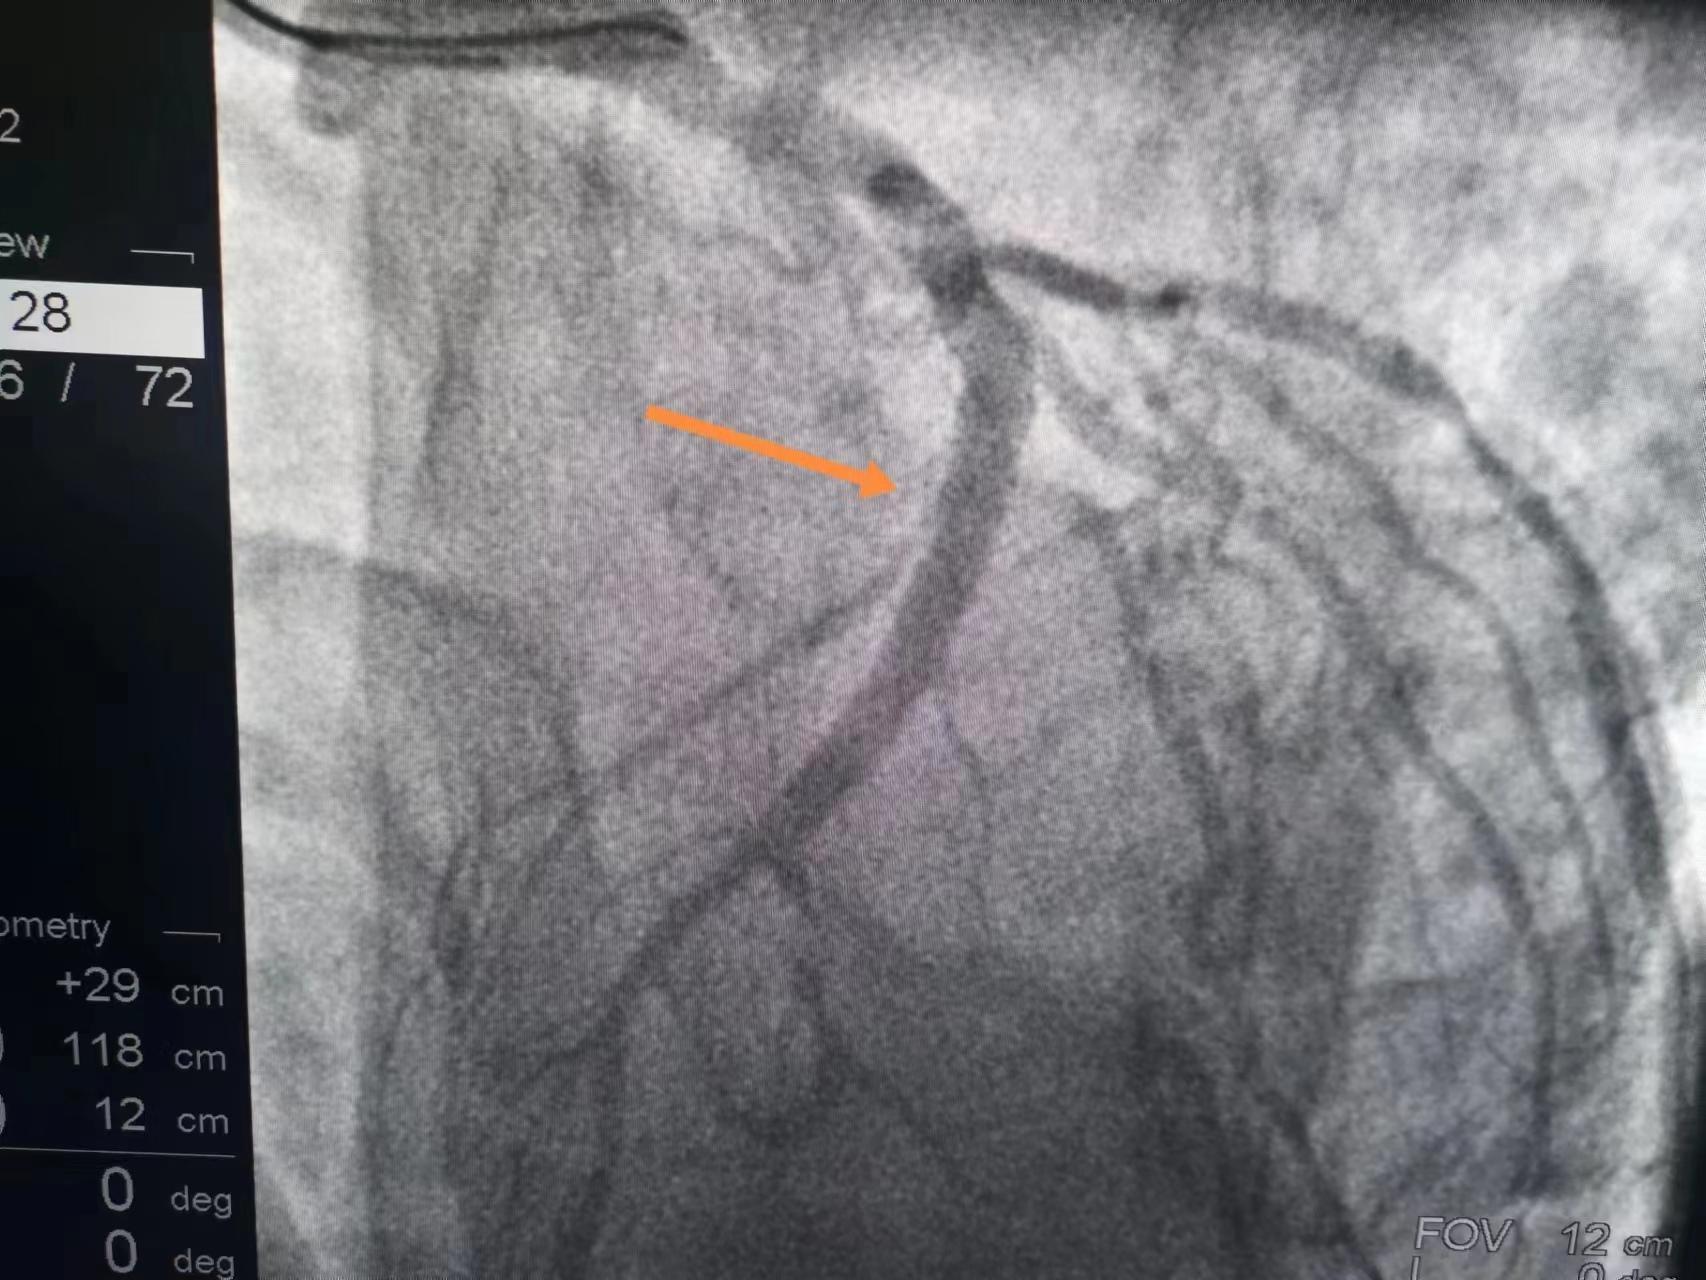

程先生被转至我们医院,造影发现,大家可以看到,心脏左侧的大血管中段有一个严重的狭窄,但血流是通畅的。这就说明溶栓成功了,所以非常感谢溶栓的医院。

大家也可以直观地看到,溶栓成功后的血管,即使血流恢复,但固定狭窄还是非常严重的,这种狭窄心肌缺血心绞痛的风险很大,而且心肌梗死风险也很大,所以还是植入了一枚支架,做完支架大家再看这血管,管腔完全恢复了,那么以后保养好,就不会心绞痛,心肌梗死的风险也会大大降低。